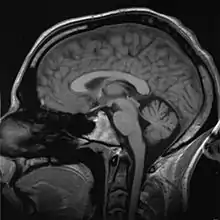

Medical imaging

Medical/biomedical imaging is a major segment of medical devices. This area deals with enabling clinicians to directly or indirectly "view" things not visible in plain sight (such as due to their size, and/or location). This can involve utilizing ultrasound, magnetism, UV, radiology, and other means.

Imaging technologies are often essential to medical diagnosis, and are typically the most complex equipment found in a hospital including: fluoroscopy, magnetic resonance imaging (MRI), nuclear medicine, positron emission tomography (PET), PET-CT scans, projection radiography such as X-rays and CT scans, tomography, ultrasound, optical microscopy, and electron microscopy.